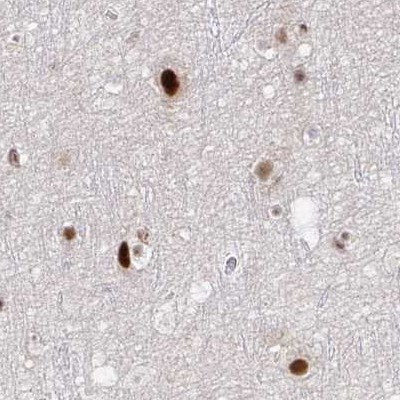

Immunohistochemical staining of human cerebral cortex, colon, kidney and testis using Anti-PSMD7 antibody HPA049824 (A) shows similar protein distribution across tissues to independent antibody HPA056069 (B).